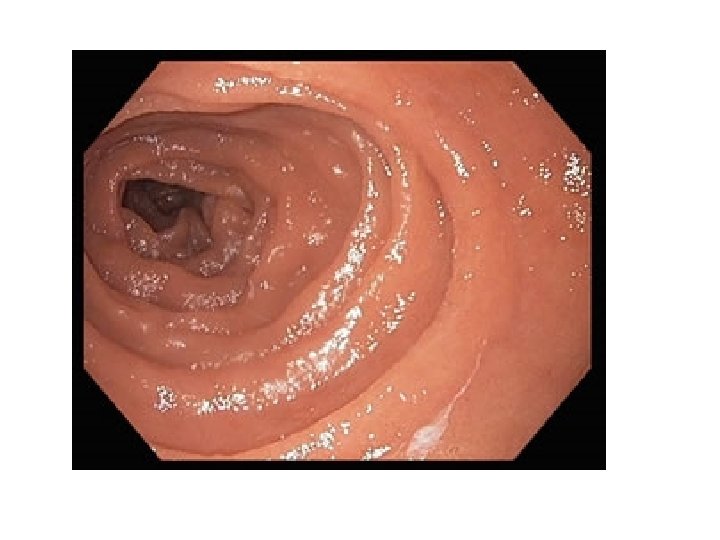

• 3 muscular layers: outer longitudinal, middle circular, and inner oblique to produce churning action • Rugae: large folds that allow stomach to stretch • Chyme: paste-like substance that forms when food begins to be broken down

Small Intestine • • Measures 6 meters in length Major absorptive organ Chyme takes 3 -5 hours to pass through Contains enzymes to further breakdown food • Contains secretions for protection against chyme’s acidity

Parts of Small Intestine • Duodenum: - 25 cm long - contains absorptive cells, goblet cells, granular cells, endocrine cells - contains microvilli and many folds - contains bile and pancreatic ducts • Jejunum: 2. 5 meters long and absorbs nutrients • Ileum: 3. 5 meters long